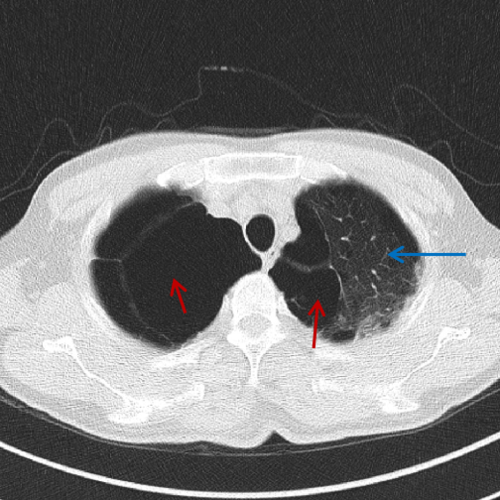

这竟然不是简单的"肺大泡",可能是"囊性肺癌"!

术前胸部ct提示两肺多处巨大疱病变

遂来我院就诊,查胸部ct可见双肺广泛肺大泡,右肺肺大泡较左侧更为明显